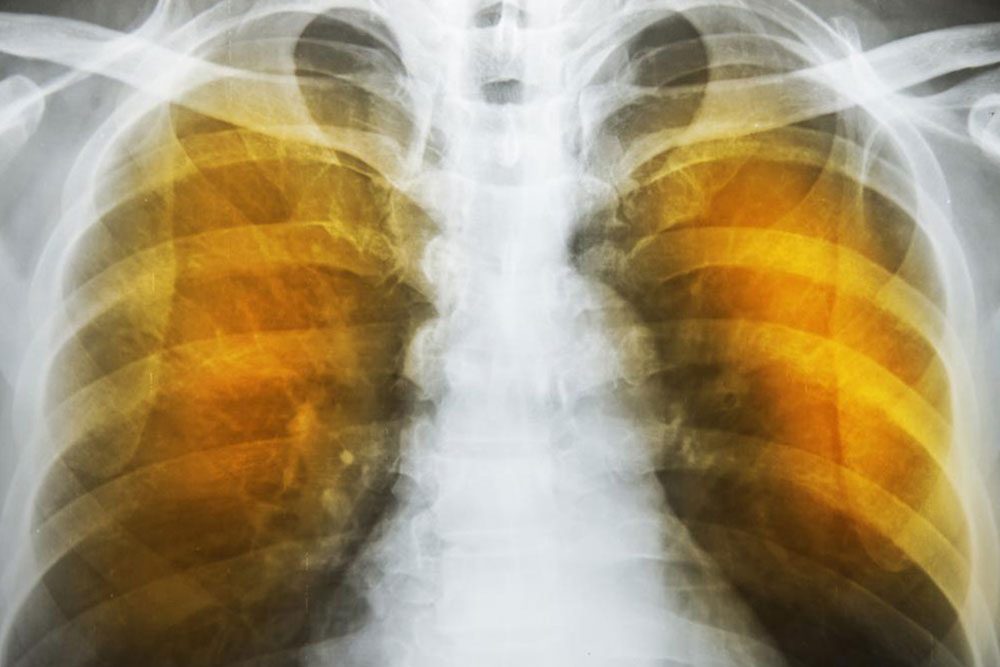

Emphysema is an oppressive respiratory disorder which results from the disintegration of the alveoli, i.e., the tissues where the interchange of gas with blood takes place. Destruction in any large scale will reduce the gas transfer area and the process of gas transfer itself, leading to oxygen starvation or hypoxia.

Another complication is the alveoli becoming weaker, and then starting to break. When this assumes larger scale, vacant spaces are formed called bullae. This reduces the gas transfer area as well as the capacity of the lung to expand. These are often have to be surgically removed to allow more space for the lung to expand. In the ultimate case, lung transplant becomes the only choice. Another scenario is a large-scale disintegration of alveoli that can cause pneumothorax, which is a condition in which the chest cavity is filled with air and the lungs collapse. This is a very serious condition if not fatal.